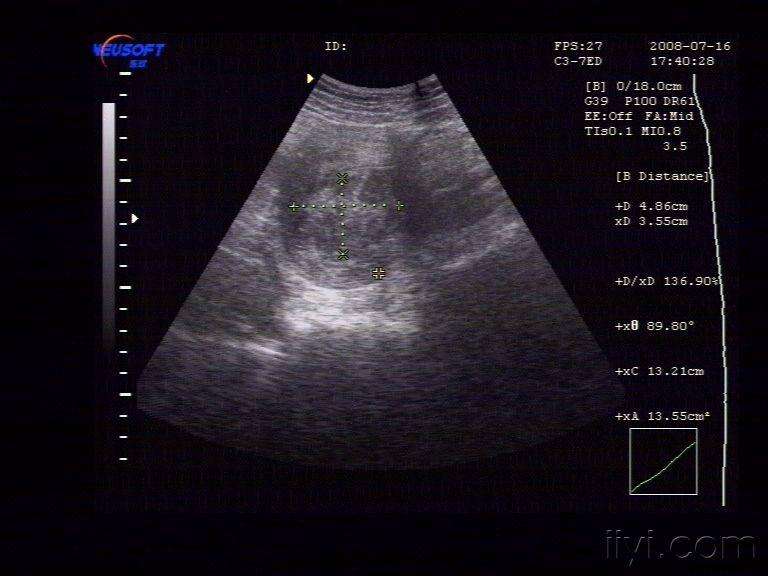

子宫腔内低回声占位,考虑什么

子宫左附件区占位并腹水(超声,病理已公布)